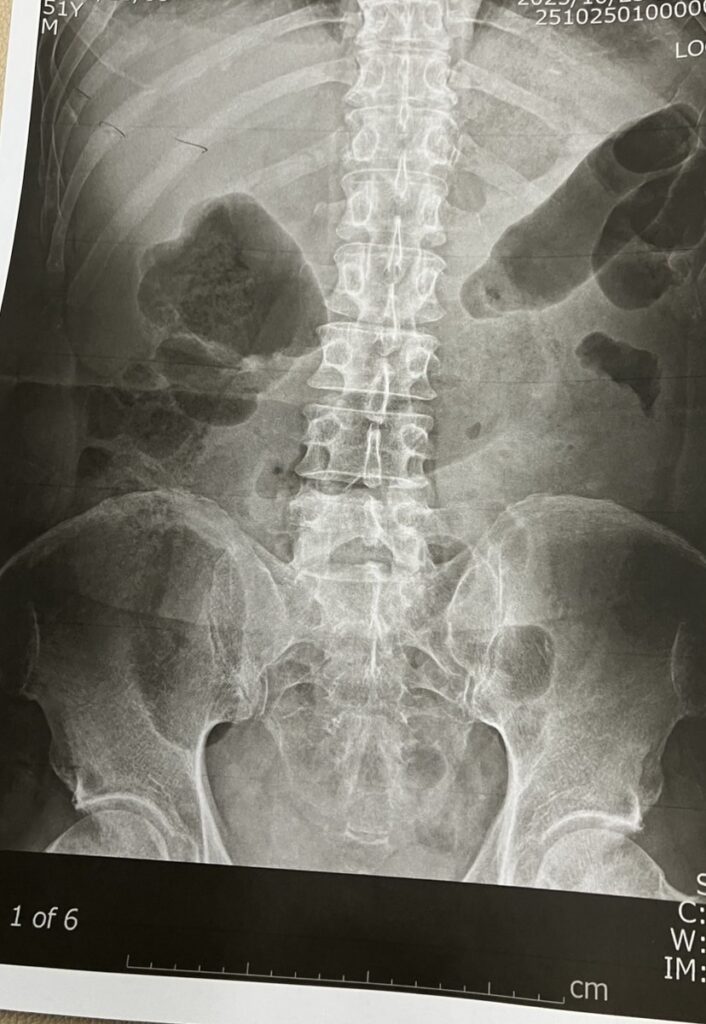

搬送先の病院で検査を受けた結果、肋骨4本の骨折と診断されました。

幸い内臓への損傷はなく、入院による安静と経過観察で回復が見込まれるとのことでしたが、支援者としてその場に居合わせた私は、改めて生活支援とは健康管理の延長でもあると痛感しました。